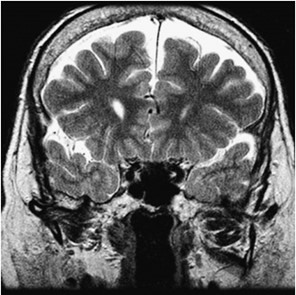

En primer lugar, se puede tratar el caso de los adictos al cannabis, cuya droga tiene efectos sobre el sistema endocannabinoide y en las áreas cerebrales vinculadas con la regulación de las emociones y el estrés. Un estudio de casos y control demostró mediante tomografía por emisión de positrones (PET) cómo la exposición crónica al cannabis, específicamente al THC, reduce la respuesta cerebral a la dopamina, y por ende, mayor puntuación de emocionalidad negativa en los adictos a esta sustancia respecto de los que no lo son. Esto se demostró con el uso de fármacos estimulantes, como el metilfenidato. Este mismo fenómeno también se ha observado con drogas como el alcohol, la cocaína y la nicotina. El cannabis también ocasiona una disminución en el metabolismo de la glucosa cerebral en el cuerpo estriado, tálamo y mesencéfalo(15) (ver Imagen 3).